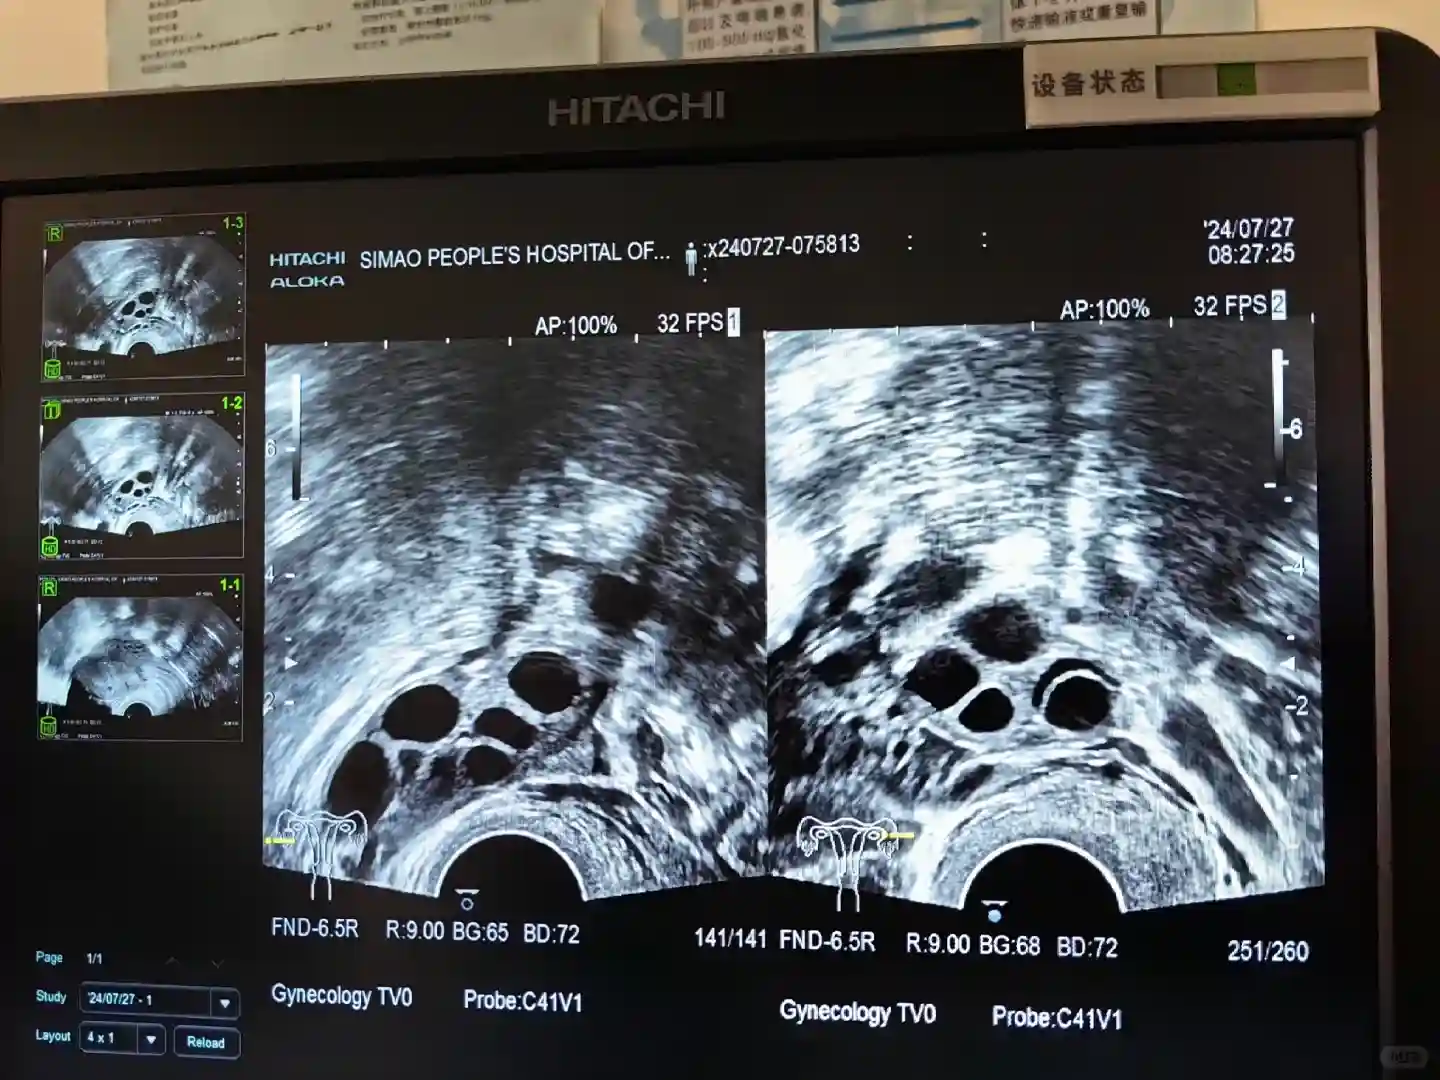

确认方案后就带上促排药回国了(图3)➡️7月23日月经来第二天开始打促排针,我的计量是250(图4)针像胰岛素一样很小很细➡️医生交代第5天需要去做卵泡检测,我就在当地的妇科做了B超左右卵巢各有6个(图5)➡️第六天开始加打一针保卵针(图6)需要调一下药,换一下针头,但是也很细,略比果纳芬粗一点点🤏但也不疼➡️一直到7月29日到大马,30日一早回到医院扫描卵巢,确定8月3日取卵➡️8月1日19:15打了破卵针(最后一支针),也就是所谓的夜针(图7)➡️8月2日晚饭后吃了两颗排泄的药后禁食➡️8月3日一早7:45全麻取卵➡️成功取出16颗卵,成熟的6颗已做ICSI➡️等待8月5日的受精成绩个人感觉整个促排过程没有任何痛苦,打的针都很细,头5天都是对象帮忙打的,第6天我就开始自己打了,只是打之前心里有一丝恐惧其实一点也不疼。我每天都会走15000-20000步,加上练瑜伽,一定要适当运动,保持愉悦的心情。我全程也没有腹涨的感觉,肚子会有点变松但是正常的,R头后几天会有些疼,但也还好,就像生理期一样的。目前我也取完卵躺在床上休息,没什么特别的感觉,有点点姨妈痛吧,没出血。喝了椰子水,电解水,正常排了好几次尿,还下楼买了些东西,目前没有腹水情况。想发这篇文章主要是想告诉各位姐妹们不要害怕,其实我没开始做之前也有身边的朋友说会很痛苦,我也畏惧过,但其实一点都不难受,所以整个促排过程一定要放轻松,要适量运动,不要跑步,不要练腹,不要倒立;快走瑜伽泡脚,补充蛋白质,早睡都有助于排卵。我目前算是一个阶段告一段落了,要继续开始养内膜了…也祝其他姐妹一切顺利#ivf之旅 #马来西亚生殖#试管 #促排